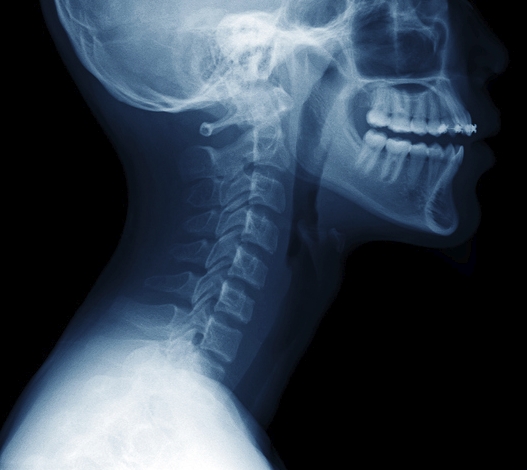

일자목은 본래 C자 형태로 휘어 있어야 하는 경추(목뼈)의 곡선이 무너지면서 일직선처럼 펴진 상태를 말합니다. 겉으로 보기에는 큰 차이가 없어 보여도, 머리의 무게가 그대로 목과 어깨에 실리면서 다양한 증상으로 이어집니다. 주변 사람들 이야기를 들어보면 목이 뻣뻣하게 굳은 듯한 느낌이 계속되고, 고개를 숙이거나 젖힐 때 어딘가에서 뻐근하거나 저릿한 느낌이 든다고 말하곤 합니다. 하루 종일 컴퓨터 앞에 앉아 있는 직장인이나 스마트폰을 자주 보는 사람들에게 흔하게 나타나는 증상이기도 하지요.

일자목과 거북목은 비슷한 듯하지만 그 원인과 진행 양상에서 차이가 있습니다. 일자목은 경추의 C자 곡선이 사라지며 직선으로 변한 상태이고, 거북목은 그보다 더 심화되어 목이 몸통보다 앞으로 빠져나온 체형까지 바뀐 경우입니다. 쉽게 말해, 일자목은 정적인 구조의 변화라면 거북목은 역동적인 자세의 변형이라고 할 수 있죠. 일자목은 비교적 초기에 발견되면 교정이 어렵지 않지만, 거북목은 어깨 말림이나 등 근육의 긴장, 허리 통증까지 이어지기 때문에 더 복잡한 교정 과정이 필요합니다.